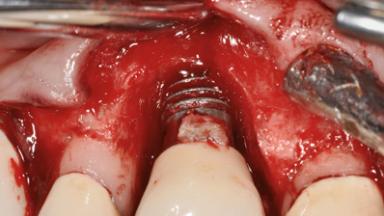

A 73-year-old woman was referred to the Division of Periodontology (University of Geneva School of Dental Medicine) after repeated unsuccessful treatment of a peri-implant infection. She was systemically healthy and did not smoke. The patient’s history revealed that, three years earlier, an immediate implant (Straumann Tapered Effect RN 4.8/4.1; Institut Straumann AG, Basel, Switzerland) had been inserted to replace the upper right central incisor. A metal-ceramic crown had been delivered using an adhesive resin cement. One year later, the patient had consulted another dentist due to discomfort in the soft tissues in the implant region. There was a suppurating peri-implant pocket, 10 mm deep. Peri-implant bone loss and excess luting cement were seen on the radiograph. The situation was treated with non-surgical debridement, amoxicillin, and repeated submucosal irrigation with a chlorhexidine digluconate solution. The patient was referred after the suppuration had persisted for several months.